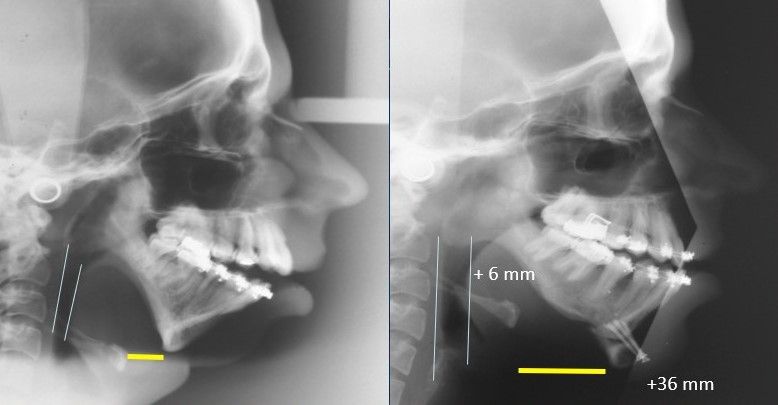

For over 30 years, Dr. Guerrero has made it his mission to improve the lives of his patients through specialized surgical care that restores function and comfort. Dr. Guerrero’s work embodies precision, compassion, and a dedication to patient well-being. Corrective jaw surgery is one of the advanced services offered, designed to address functional issues and enhance the quality of life for those who need realignment and reconstruction.